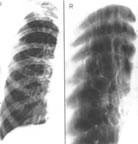

《呼吸系統疾病病理》肺炎

慢性阻塞性肺病、肺炎、矽肺、肺癌、鼻咽癌是當前呼吸系統的常見病。引起肺炎的病原體繁多,病毒、支原體、衣原體、細菌、黴菌等均可感染肺臟。病變分布可以是大葉性、小葉性和間質性(不典型性)。典型的大葉性肺炎由肺炎鏈球菌引起,病變累及整個大葉或大葉大部,屬纖維素性炎,已不多見。小葉性肺炎在肺內形成散在的小葉性或小葉融合性病變,屬化膿性炎。小葉性肺炎由多種細菌引起,醫院內肺炎的病原體多具抗藥性。原發性不典型性肺炎實際上屬間質性肺炎,以肺泡間隔內淋巴細胞、單核細胞浸潤為主,可由病毒、支原體、衣原體引起。

慢性支氣管炎、慢性阻塞性肺氣腫是常見的肺疾病。細支氣管的炎症、阻塞,引起通氣障礙,導致肺內殘氣增多。肺內彈性蛋白酶增多,活性增高,破壞肺的彈力組織。以上兩個致病因素長時間作用,引起慢性阻塞性肺氣腫。全腺泡型肺氣腫以全小葉肺泡擴張為特點,與先天性α1-抗胰蛋白酶缺乏有關。腺泡中央型肺氣腫病變以呼吸性細支氣管囊性擴張為主。矽肺是吸入二氧化矽粉塵而引起的塵肺,矽結節和肺間質廣泛纖維化嚴重破壞肺的結構和功能。雖然肺疾病、肺血管疾病、胸廓疾病均可導致肺原性心臟病。但以肺氣腫、肺纖維化常見。肺動脈高壓是肺心病發生的關鍵。表現為右心肥大和擴張。